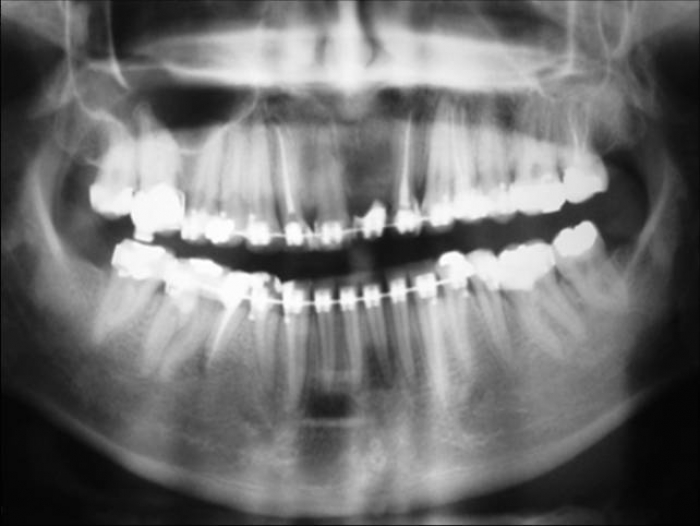

Raio X inicial